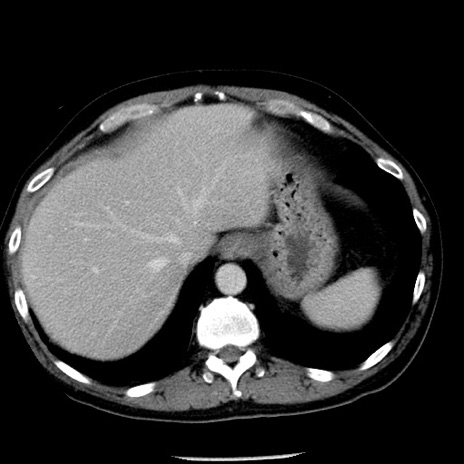

症例29(横断像)

【症例】40歳代男性

【現病歴】2日前から胃痛あり。徐々に周期的な激痛に変化した。本日になっても激痛があるため受診。

【身体所見】意識清明、BT 38-39℃台あり、腹部:膨満、やや硬、右下腹部に圧痛あり。

【データ】WBC 8500、CRP 23.26